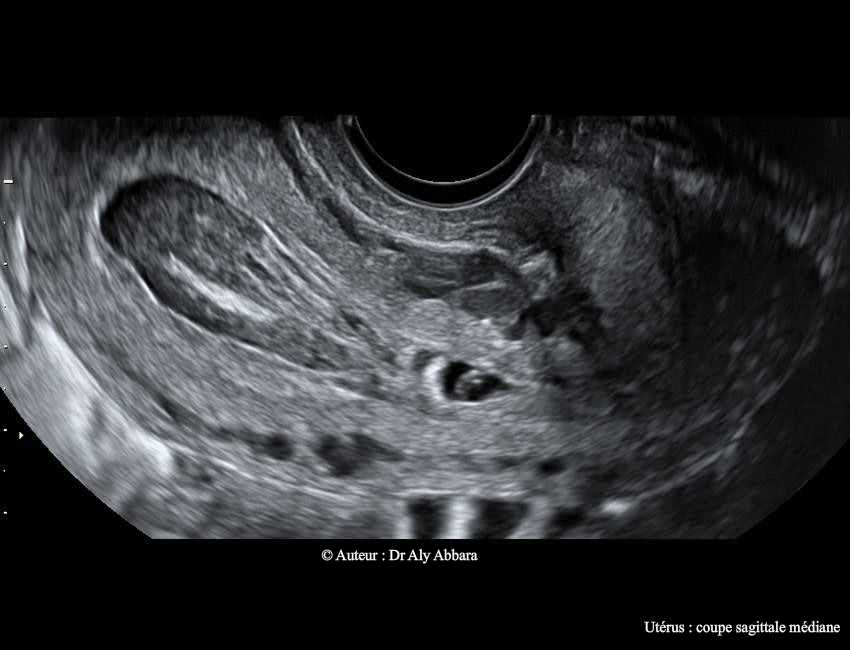

• Images échographiques montrant l'évolution spontanée d'une grossesse débutante à insertion basse, dans la zone isthmique de la cavité utérine (grossesse isthmique utérine).

• Échographiquement on peut observer à travers les images ci-dessus que le sac gestationnel qui s'est implanté dans la région isthmique de la cavité utérine continue à évoluer lors du contrôle, à 2 jours et à 4 jours après l'examen initial, avec l'apparition d'une image embryonnaire munie d'une activité cardiaque et mesurant, à J4, 2,3 mm.

Le sac gestationnel était partiellement décollé au niveau de son pôle supérieur dès l'examen initial. Ce décollement s'élargissait à J2 et à J4 ; il est à l'origine (dès l'examen initial) de la formation d'une hématométrie qui s'aggravait au cours du développement de la grossesse (36 ml à J4 et 47 ml à J6) ; deux éléments participaient à sa formation : le décollement progressif du sac gestationnel et l'effet de bouchon exércé par ce sac sur le canal cervical en l'obstruant au niveau de son orifice interne.

A J6 : on observe l'arrêt de l'activité cardiaque embryonnaire et l'écrasement du sac gestationnel et son engagement partiel dans le canal cervical sous l'effet des contractions utérines et la pression exercée par la volumineuse hématométrie.